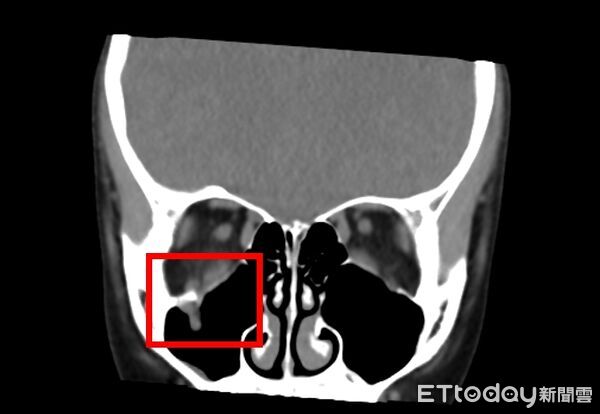

▲女童眼窩骨折,眼底出現裂口,眼窩組織掉入上顎竇,導致眼球活動受到影響。(圖/中山附醫提供,下同)

邱昱瑋說明,眼窩骨折多發生於眶底,常因棒球、拳頭或碰撞等鈍力造成,若發生於兒童,因骨骼較軟,容易出現線性爆裂性骨折,也就是骨頭破裂後瞬間又回彈復位,反而將眼眶內肌肉或軟組織夾住,導致複視及眼球運動受限;此類骨折往往不明顯,容易被忽略,若延誤處理,併發症風險將明顯提高。